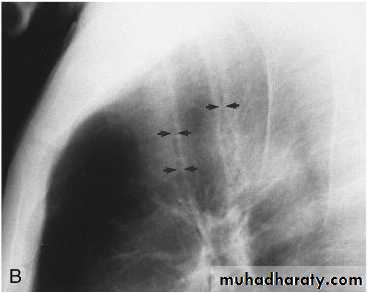

Miliary Tuberculosis. A cone-down view of a frontal radiograph demonstrates innumerable micronodular opacities characteristic of micronodular (miliary)

interstitial disease.

Transbronchial biopsy demonstrated caseating granulomas containing acid-fast bacilli.

Miliary TB

a frontal radiograph demonstrates innumerable micronodular opacities characteristic of micronodular (miliary) interstitial disease. Transbronchial biopsy demonstrated caseating granulomas containing acid-fast bacilli.Tuberculoma